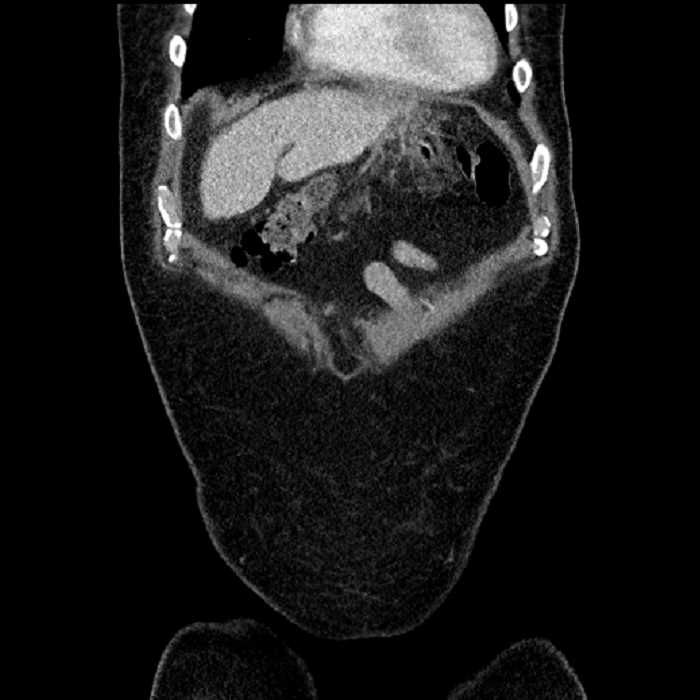

Age: 63

Sex: Male

Indication: Abdominal pain

• Mild mural thickening of a segment of the sigmoid colon with adjacent fat stranding and a 1.5 cm fluid and gas collection along the tip of an inflamed diverticulum

• Loss of the normal fat plane between this collection and adjacent loops of small bowel, which demonstrate mural thickening

• No bowel obstruction

• Hepatic abscess

Acute sigmoid diverticulitis complicated by a small contained perforation and a large abscess in the right hepatic lobe. Additional small subcapsular abscesses along the anterior margin of the left hepatic lobe.

Additionally, loss of the normal fat plane between the peridiverticular collection and adjacent thickened loops of small bowel raises the potential for an enterocolonic fistula.

Hepatic abscess showing the double target sign with low density internally surrounded by a thin inner enhancing rim (red arrow) and ill-defined outer low density rim (yellow arrow). Blue arrow indicates an internal septation. Red arrows: additional smaller subcapsular abscesses. Red arrow: focal contained perforation associated with diverticulitis.